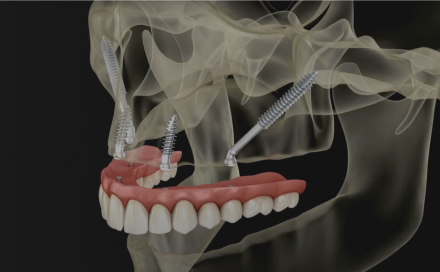

Zygoma to długie implanty (30–60 mm), wykorzystujące zakotwiczenie w kościach jarzmowych, które zapewnia lepszą stabilizację pierwotną oraz siłę wtórnego mocowania implantu. Daje to możliwość szybkiego/natychmiastowego obciążenia implantów odbudową protetyczną.

Implanty Zygoma są dużo dłuższe od typowych implantów i występują w długościach od 30 do 60 mm, aby w sytuacji braku kości w strefie wyrostka zębodołowego mogły dotrzeć i być mocno ustabilizowane w trzonie kości jarzmowej, znajdującej się w odległości kilku centymetrów od pozycji zębów.

Klasyczny implant Zygoma ma zróżnicowaną szerokość trzonu: 4,5 mm – 1/3 górnej i 4 mm – 2/3 dolnej, która uwzględnia optymalne jego mocowanie zarówno w zanikłej kości szczęki u dołu, jak i mocnej strukturze kości jarzmowej u góry, która jest w tych przypadkach podstawą stabilizacji implantu.

Kolejna istotna różnica w budowie w stosunku do tradycyjnych implantów to kąt główki, który może wynosi 45° oraz 0°. Koncepcja 45° wynika ze skośnej pozycji implantu mocowanego w zatoce szczękowej i trzonie kości jarzmowej. Kąt szyjki 45° upraszcza i optymalizuje montaż rozwiązań protetycznych na platformach implantów Zygoma bez użycia łączników MultiUnit. Koncepcja 0° uwzględnia uproszczenie chirurgicznej części procedury, natomiast protetyczna część optymalizowana jest dzięki użyciu specjalnych łączników kątowych MultiUnit – jak w metodzie All-on-4.

Klasyczny protokół ZYGOMA

Przeznaczony dla pacjentów z brakiem dostatecznej ilości kości szczęk w zakresie całego górnego łuku. Protokół implantoprotetyczny zakłada wprowadzenie podczas procedury 4 implantów Zygoma.

Protokół QUAD ZYGOMA

Przeznaczony dla pacjentów z brakiem dostatecznej ilości kości w zakresie całego górnego łuku. Rozwiązanie zakłada 4 implanty jarzmowe, 4 łączniki MultiUnit, natychmiastowy tymczasowy most wykonany z akrylu, o ile jest to możliwe.